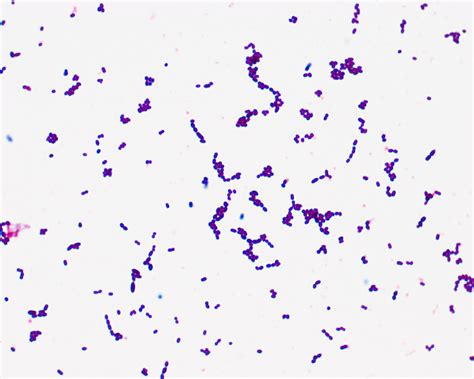

E Faecalis Gram Stain

For *Enterococcus faecalis*, the E Faecalis Gram Stain is particularly important because it helps to confirm the Gram-positive nature of the bacterium. This information is crucial for further identification and treatment strategies. The Gram stain also provides insights into the morphology of the bacterium, which is typically seen as pairs or short chains of cocci.

• Drying and Examination: Allow the slide to air dry and then examine it under a microscope. Gram-positive bacteria, including *E. faecalis*, will appear purple, while Gram-negative bacteria will appear pink or red.

Interpreting the results of an E Faecalis Gram Stain involves observing the stained bacteria under a microscope. Gram-positive bacteria, such as *E. faecalis*, will appear purple or blue due to the retention of the crystal violet stain. The morphology of *E. faecalis* is typically seen as pairs or short chains of cocci, which helps in differentiating it from other Gram-positive bacteria.